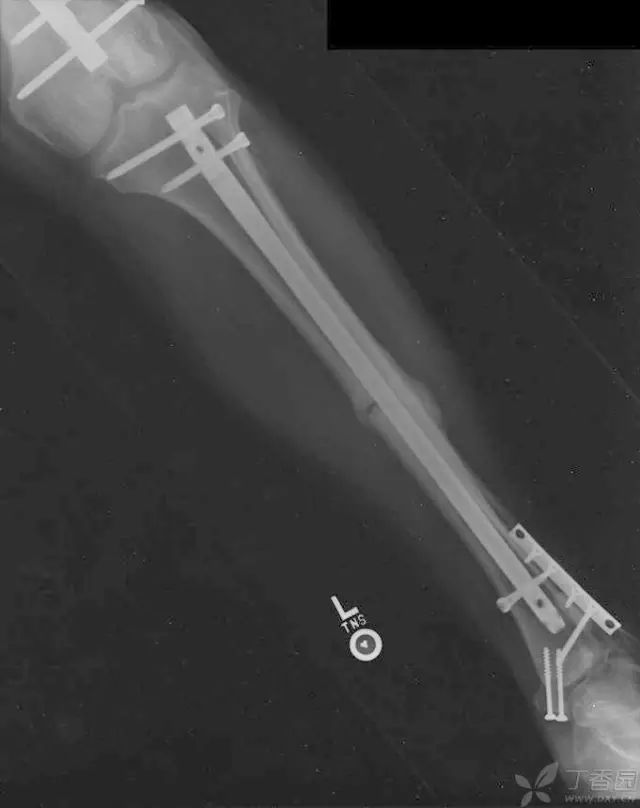

病例三

创口清创、大量冲洗以后一期外固定支架固定,缺损区域抗生素骨水泥填充

二期回植,更换为钢板内固定

回植后 8 个月,骨折无感染迹象

另一例 48 岁男性,大块的胫骨骨折块,12 周以后从腹部皮下取出骨折块,图 B,去除再血管化的软组织